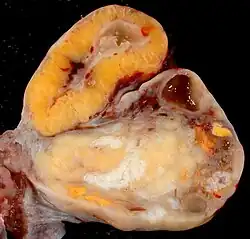

Corps albicans

Le corps albicans (ou corpus albicans) est aussi appelé corps blanc ou corps fibreux (la dégénérescence est fibreuse, les cellules glandulaires se transforment en tissu conjonctif dense[réf. nécessaire]). Il apparaît lors de la lutéolyse (en)) du corps jaune, à la fin de la phase lutéale ou, après que le placenta a pris le relais pour la production d'hormones.[réf. nécessaire]